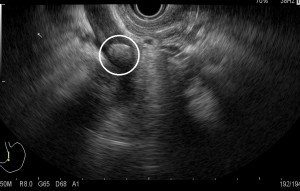

Common bile duct (CBD) stone